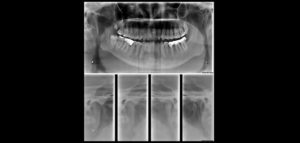

La reabsorción radicular interna (RRI) es una afección inflamatoria que resulta en la destrucción progresiva de la dentina intra-radicular a lo largo de los tercios